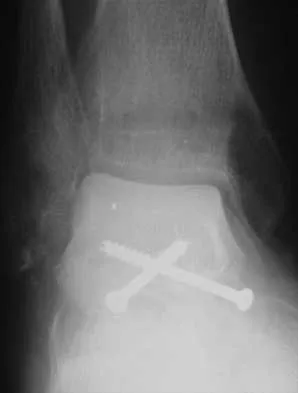

A 57-year-old man has had right ankle pain for the past 10 months following an injury that went untreated. Radiographs are shown in Figures 30a through 30c. Management should consist of